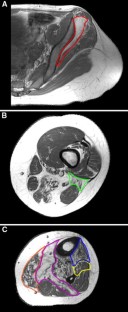

GNE myopathy (MIM 600737) is an autosomal recessive muscle disease caused by mutations in the UDP-N-acetylglucosamine 2-epimerase/N-acetylmannosamine kinase (GNE) gene. Besides the typical phenotype, characterized by the initial involvement of the distal leg muscles that eventually spreads proximally with sparing of the quadriceps, uncommon presentations with a non-canonical clinical phenotype, unusual muscle biopsy findings or both are increasingly recognized. The aim of our study was to characterize the imaging pattern of pelvic and lower limb muscles in GNE myopathy, thus providing additional diagnostic clues useful in the identification of patients with atypical features. We retrospectively evaluated muscle MRI and CT scans of a cohort of 13 patients heterogeneous for GNE mutations and degree of clinical severity. We found that severe involvement of the biceps femoris short head and, to a lesser extent, of the gluteus minimus, tibialis anterior, extensor hallucis and digitorum longus, soleus and gastrocnemius medialis was consistently present even in patients with early or atypical disease. The vastus lateralis, not the entire quadriceps, was the only muscle spared in advanced stages, while the rectus femoris, vastus intermedius and medialis showed variable signs of fatty replacement. Younger patients showed hyperintensities on T2-weighted sequences in muscles with a normal or, more often, abnormal T1-weighted signal. Our results define a pattern of muscle involvement that appears peculiar to GNE myopathy. Although these findings need to be further validated in a larger cohort, we believe that the recognition of this pattern may be instrumental in the initial clinical assessment of patients with possible GNE myopathy.

Fig. 2